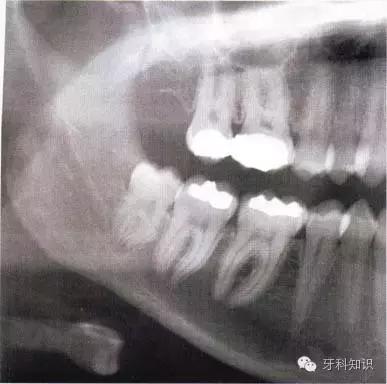

全颌曲面断层×线片。切割牙冠时应经过阻生牙远中面的牙颈部的釉牙骨质交界处

下颌升支前缘的骨吸收区有利于牙片的取出